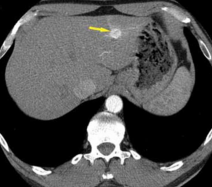

Abdominal Bruit of Unusual Origin

Ildiko Lingvay, MD; Suzanne M. Strowig, MSN, RN; Philip Raskin, MD